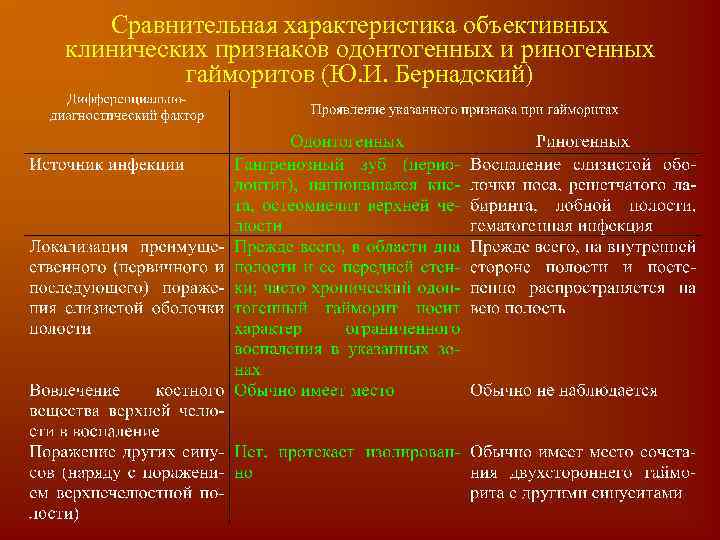

Дифференциальная диагностика заболеваний плевры